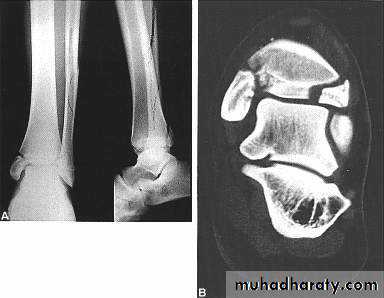

2- CT scan : such as in palvic and spine fractures and in intra articular fracures